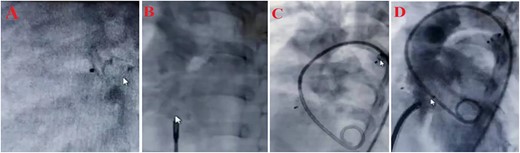

Since ASD, PDA, VSD, and pulmonary hypertension were diagnosed; it was decided to perform an interventional heart catheterization. For this purpose, PDA was closed in one step using Amplatzer ADO II type AGA, size 5–6, and then Amplatzer Septal Occluder size 15 was used to close ASD. Finally, the patient was discharged after the first stage treatment process. Six months later, a successful therapeutic interventional closure of the VSD was performed using Lifetech Symmetric Amplatzer membranous size 12 mm. Due to the lack of access to the coil, the smallest and most suitable device was used for the patient. After the treatment process, Echocardiography was used to show the position of ASD amplatzer and VSA amplatzer and there was no residual in VSD and ASD, and complications in the integrity of the aortic valve (without Aortic regurgitation or Aortic stenosis) (Fig. 1). Finally, the patient was discharged with a good general condition and no complications from open heart surgery. The treatment was successfully completed within 3 days of hospitalization. Therefore, the short length of stay in a public hospital led to a significant reduction in patient costs.

Treatment steps (A) close PDA by Amplatzer ADO II type AGA, size 5–6, (B) close ASD by Amplatzer Septal Oclotec size 15, (C) after closing PDA and ASD, D: close VSD by Amplatzer membranous, lifetec type symetric، size 12, (D) echocardiography four-chamber view after intervention.